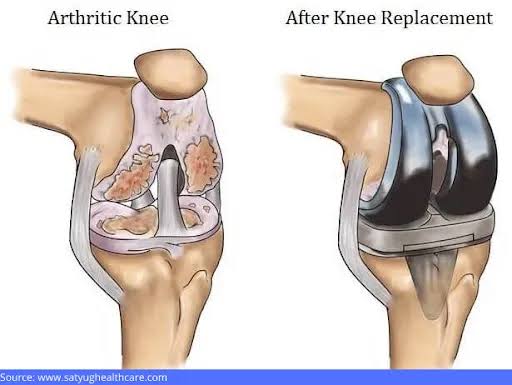

جراحی تعویض مفصل زانو در تبریز، ارومیه و اردبیل | بازگشت به زندگی بدون درد

شماره تماس. ۰۹۳۶۶۱۵۶۷۱۵ جراحی تعویض مفصل زانو چیست و چه زمانی لازم است؟ ✔️ بهترین روشهای جراحی تعویض مفصل زانو ✔️ تعویض مفصل زانو با جدیدترین تکنیکها ✔️ جراحی تعویض